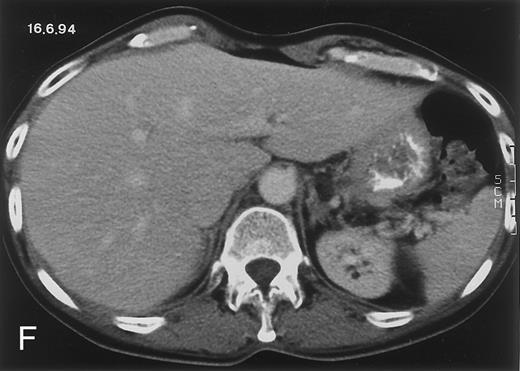

(D) On August 23, 15 days after the neutrophil count had dropped below 500/μL in the third chemotherapy cycle, focal liver lesions clearly decreased in size and number. (E) On September 30, 35 days after neutrophil recovery, multiple hepatic abscesses are seen (arrowhead). To show maximal extent of lesions the scan shown is at a slightly different level. (F) On June 16, 1994, 230 days after neutrophil recovery, the CT scan has normalized.